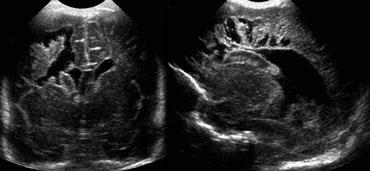

TRÁI: Hình ảnh khảo sát ban đầu cho thấy flaring. PHẢI: Hình ảnh tái khám sau một tuần cho thấy chất trắng quanh não thất bình thường.

Cần theo dõi tái khám để phân biệt flaring với PVL độ I.

Trường hợp bên trái minh họa một trẻ sinh non có hình ảnh flaring.

Tại lần tái khám, không ghi nhận sự hình thành nang và sau tuần đầu tiên, chất trắng quanh não thất trở về hình ảnh bình thường.